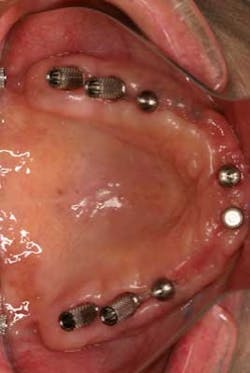

Fig. 5Using a plastic monoject syringe, acrylic is then injected around the abutments. The cotton pellet helps prevent acrylic from getting stuck inside the abutment. Once the acrylic has set completely, the cotton pellets are removed and the abutments can be unscrewed. The denture will come loose with the metal abutments integrated into the denture. The same process is then repeated for the four anterior abutments.The denture is now removed with all eight provisional metal abutments attached (Fig. 6).

Fig. 6The excess acrylic can be trimmed and any voids are filled in. The buccal flange and palatal acrylic are now removed (Figs. 7 and 7a).